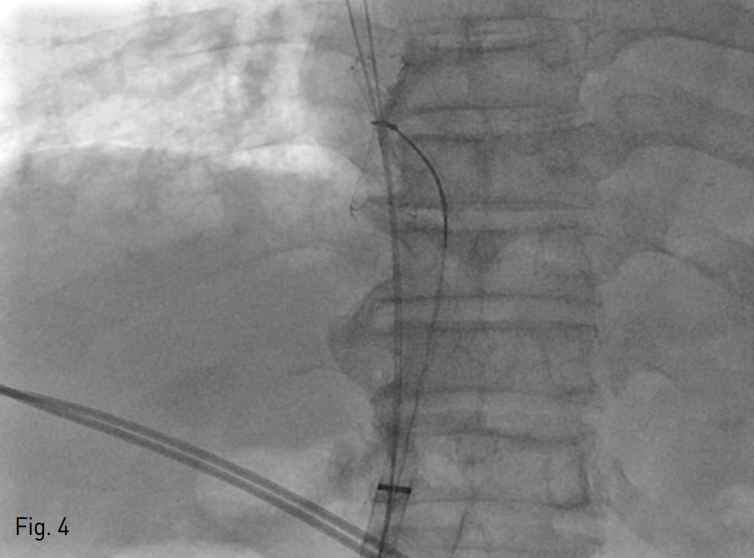

CT상 복장뼈와 대동맥 사이에서 무명정맥이 눌리고 있음 (Fig. 1).

A 72-year-old man with left arm swelling after brachiocephalic AVF. An axial CT scan shows segmental narrowing in the left innominate vein, probably due to decreased space between the aortic arch and sternum